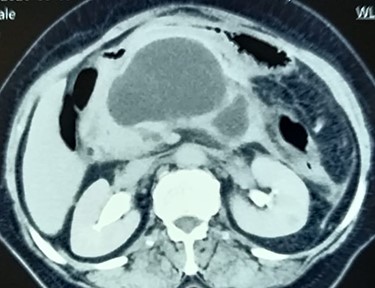

An 81-year-old female, a known case of idiopathic acute necrotizing pancreatitis, had been on percutaneous catheter drainage (PCD) for infected pancreatic necrosis at 6 weeks of onset (Fig. 1). On the eight day, she required a second PCD insertion for persistent lesser sac collection and sepsis. During PCD intervention, there was active bleeding from the catheter site which led to emergency pancreatic necrosectomy, hemostasis from the bleeding gastrocolic ligament vessel, closed lesser sac drainage and feeding jejunostomy. After surgery, she did well and was discharged on Day 15. The lesser sac drain output was clear with a raised amylase level. On the 24th day after surgery, she was readmitted for the high (300 ml/day) bilious drain output (Fig. 2). She denied any fever, vomiting or abdominal pain. She was hemodynamically stable without abdominal distention or tenderness. Her blood investigations revealed leukocytosis (13 600 cells per cubic milliliter), but normal renal function tests and serum chemistry. A diagnosis of the duodenal fistula was presumed and was kept nil per oral, intravenous fluids, antibiotics and initiation of feeding jejunostomy. She was doing well for the next 1 week with a good appetite. Contrast computed tomography (CT) excluded any peripancreatic collections, and importantly there was no oral contrast extravasation in the para-duodenal region. The drain output was persistently high (300–350 ml/day) and bilious with normal fluid amylase activity. We requested for fistulogram, which surprisingly revealed an external biliary fistula from the distal common bile duct (Fig. 3). Endoscopic retrograde cholangiopancreatography (ERCP) and bile duct stenting (7Fr × 10 cm double pigtail plastic stent) was performed, which led to the closure of the fistula over the next 7 days. At a 6-month follow-up, the patient is doing well.

Contrast CT abdomen showing walled-off pancreatic necrosis in the pancreatic head, close to the distal bile duct.